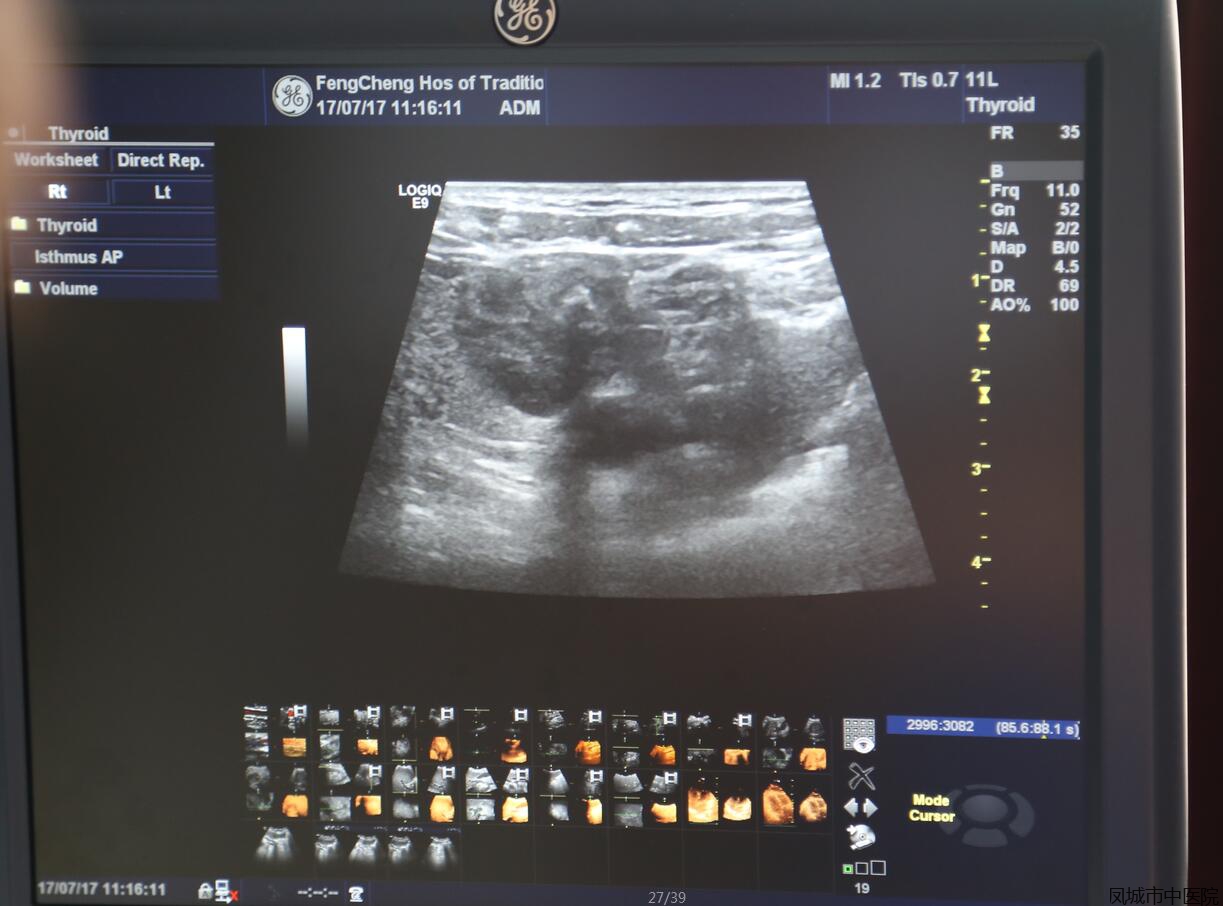

“细针吸引细胞学穿刺活检术”治疗甲状腺结节

如今,凤城市中医院开展了细针吸引细胞学穿刺活检术,可以完美解决以上难题。在结节内下一根0.7毫米的穿刺针,抽吸一些结节细胞,就可以诊断结节的性质。该方法几乎无痛,无需麻醉,既安全、又快捷。并且还可以诊断周身浅表淋巴结、前列腺结节、睾丸结节的性质。